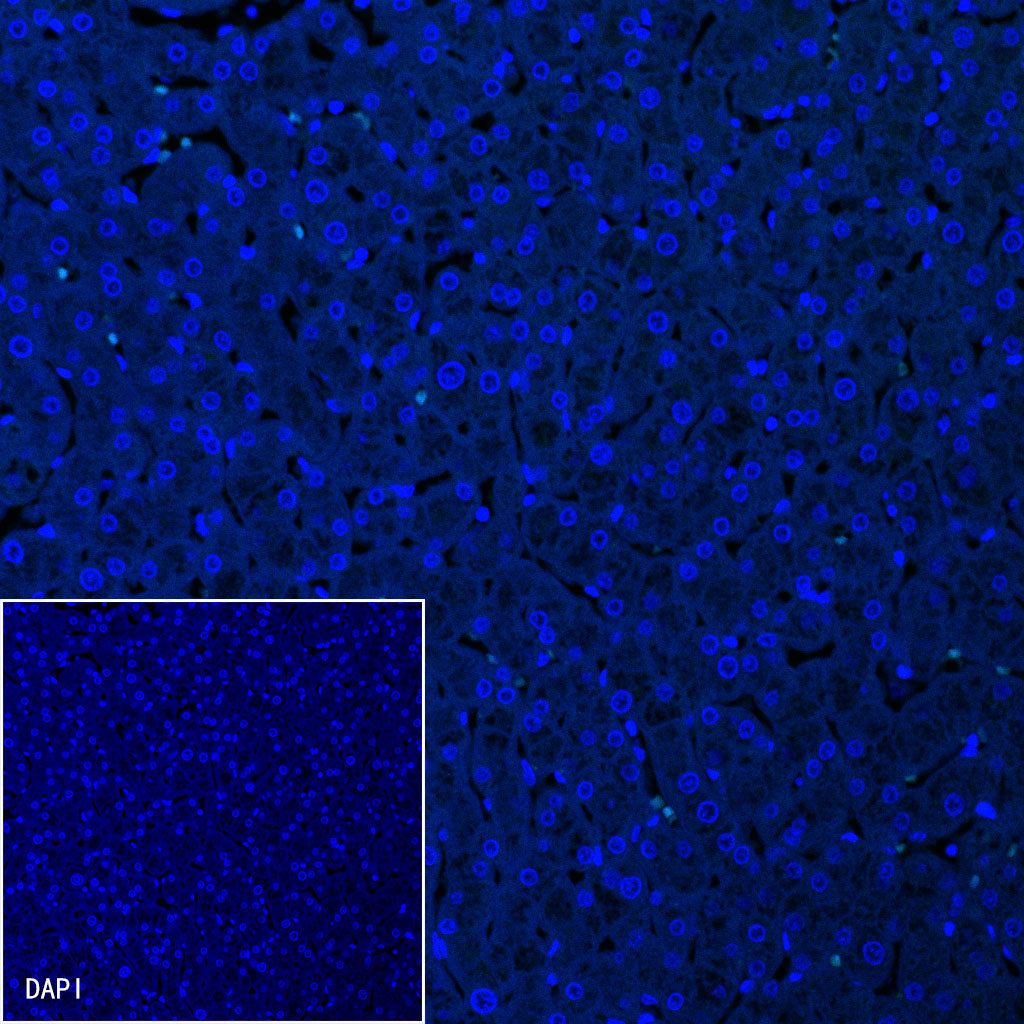

Immunofluorescence

Negative control: IF shows negative staining in paraffin-embedded human liver. Anti-Somatostatin antibody was used at 1/250 dilution (Green) and incubated overnight at 4°C. Goat polyclonal Antibody to Rabbit IgG - H&L (Alexa Fluor® 488) was used as secondary antibody at 1/1000 dilution. Counterstained with DAPI (Blue). Heat mediated antigen retrieval with EDTA buffer pH9.0 was performed before commencing with IF staining protocol.